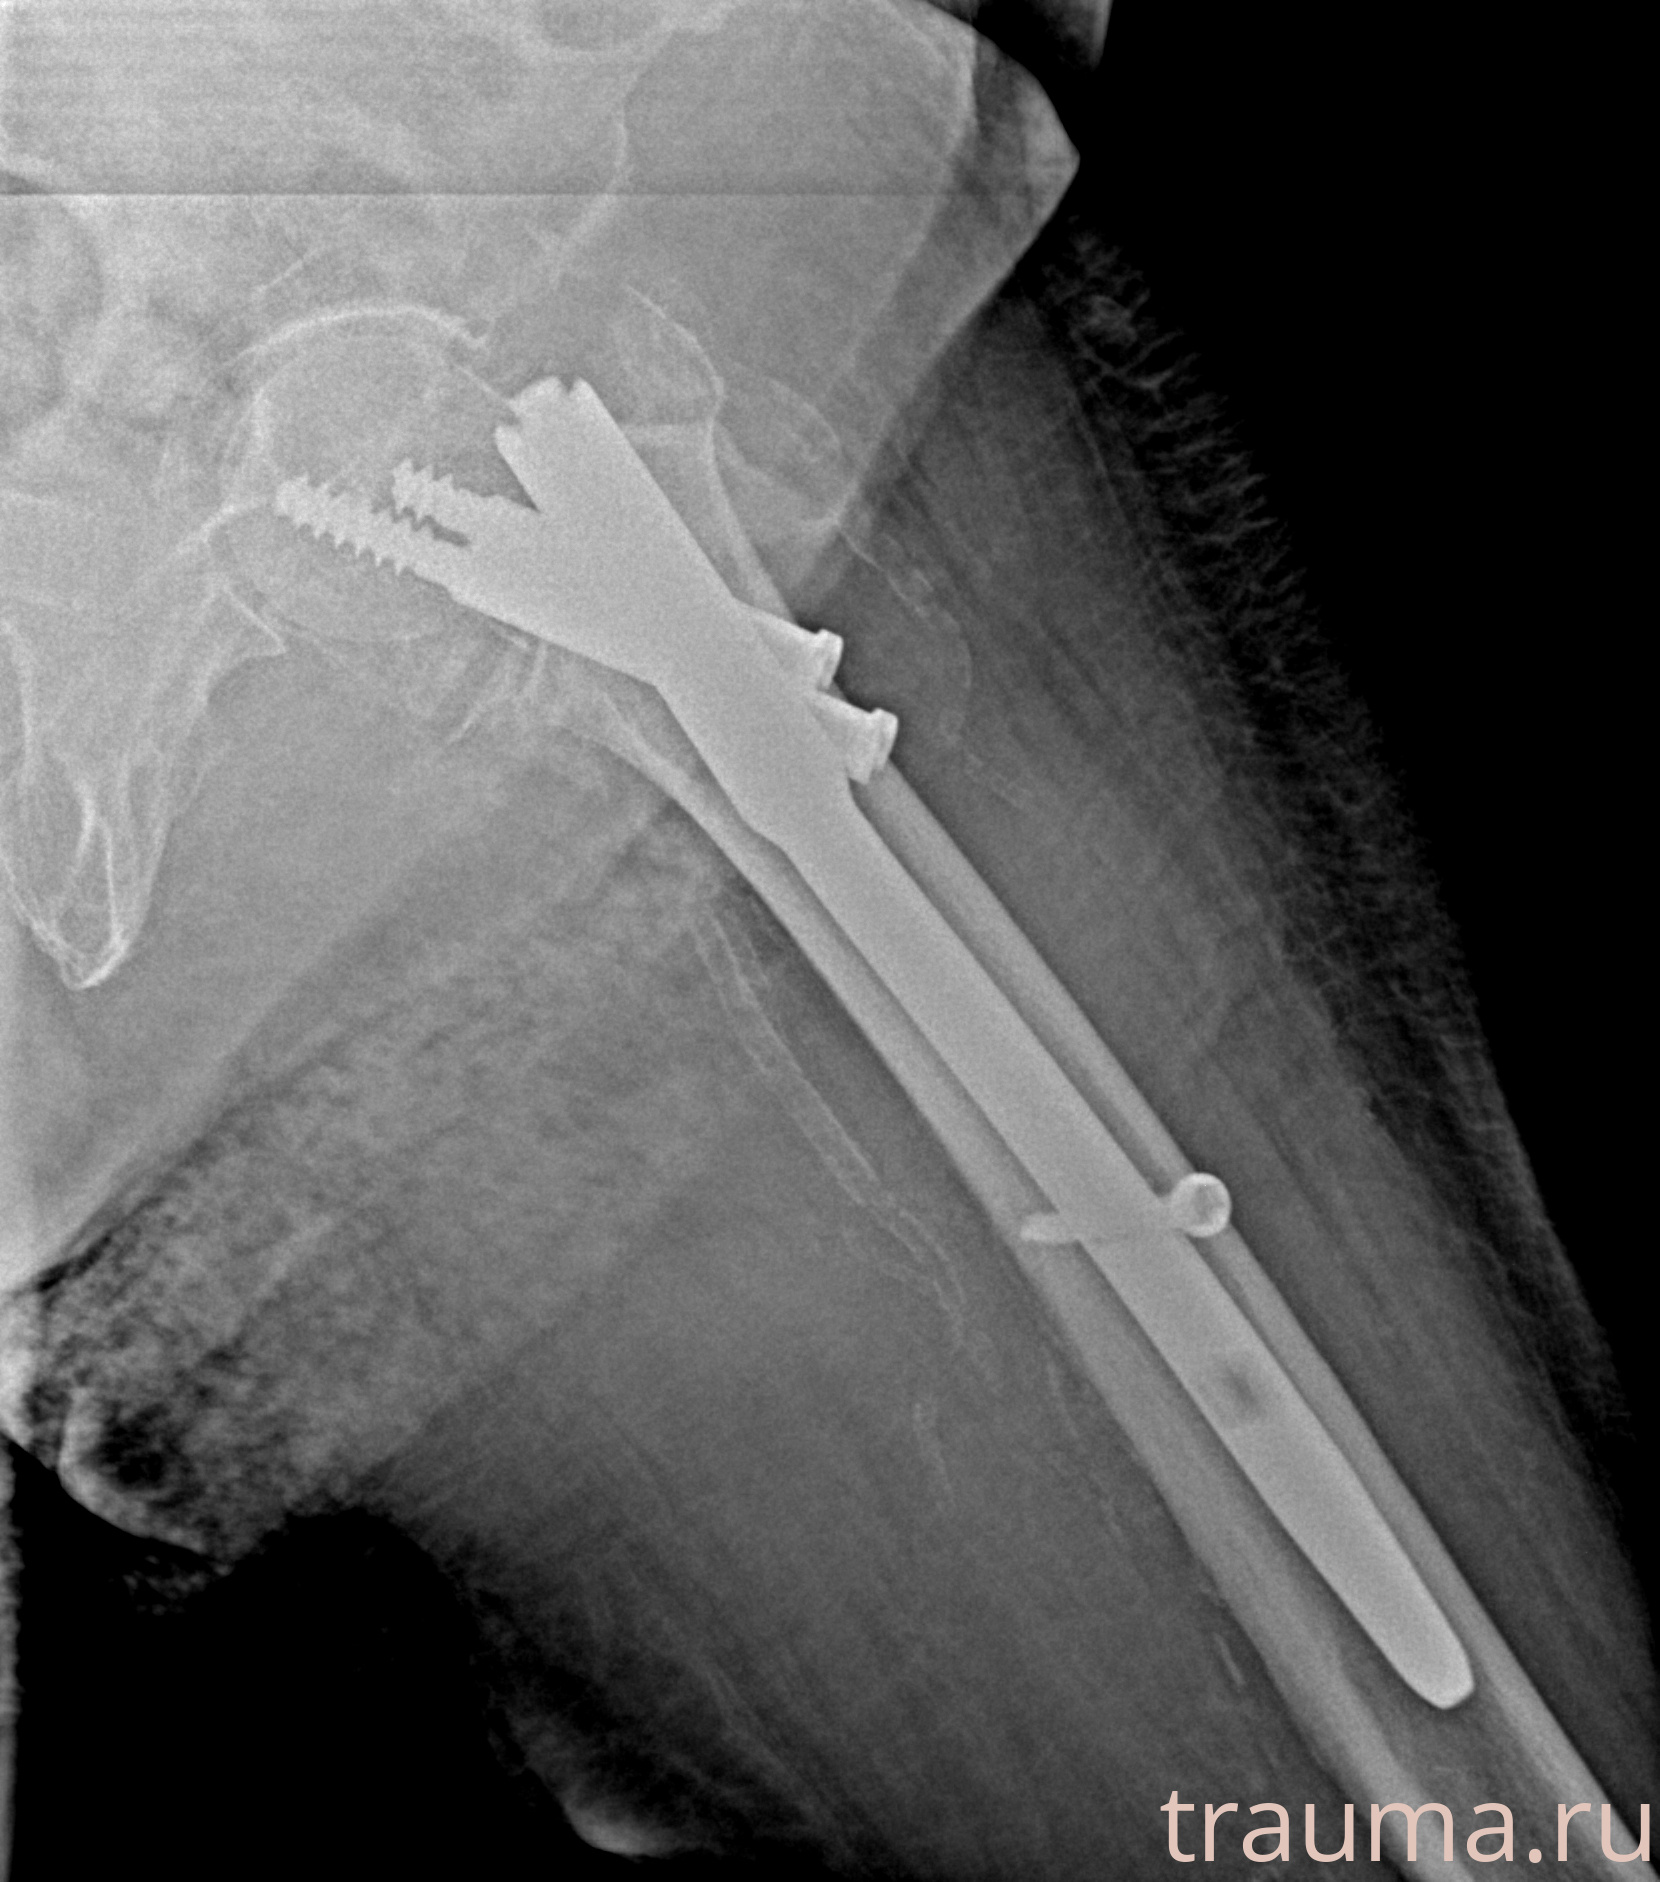

Рентгенограммы

Рентген на дому: по вашему адресу приезжает врач-рентгенолог, травматолог-ортопед с мобильным рентгеновским аппаратом, проводит диагностику травмы или заболевания, делает необходимые рентгенограммы, дает рекомендации по дальнейшему лечению. Получить качественные снимки в домашних условиях возможно благодаря уникальной методике, разработанной МосРентген Центром для института  Склифосовского

при переломе шейки бедра и пневмонии от компании МосРентген Центр - партнера Института имени Склифосовского